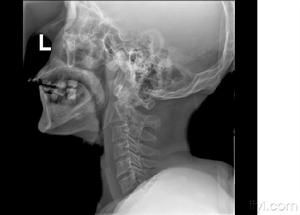

頸髓損傷X片臨床上通常可以通過X線顯示的頸椎骨折脫位的部位對頸髓損傷節段作出判斷,但有時頸椎的變化並不明顯,因此 需通過仔細檢查皮膚感覺障礙、肌肉運動障礙及反射的變化來確定。在解剖和功能的關係中,許多神經分布是交叉或重疊的,檢查時必須仔細加以辨認。有時甚至需經過反覆檢查,或從不同方向確定感覺障礙平面,才可獲得較準確的結論。頸3-4支配整個上頸部感覺,並表現為披肩狀分布的上胸部感覺。下位頸段損傷範圍需通過檢查上肢感覺分布來確定。